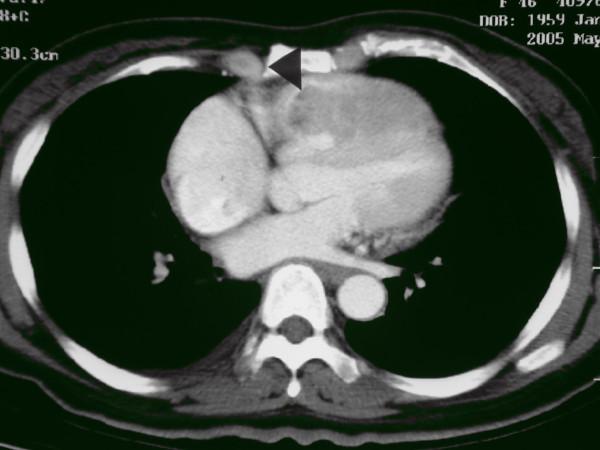

We used for the first time a right ventricular exclusion procedure for the treatment of hepatocellular carcinoma metastatic to the right ventricle. Our case report shows that this surgical option can be effective as rescue therapy for right ventricular outflow tract obstruction secondary to myocardial metastasis in critically ill patients. Most notably, this technique can prevent inadvertent dislodgement of tumor cells.

摘要

我们首次采用右心室切除术治疗转移至右心室的肝细胞癌。我们的病例报告表明,这种手术选择对于重症患者因心肌转移继发的右心室流出道梗阻可作为一种有效的挽救性治疗。最值得注意的是,该技术可防止肿瘤细胞意外脱落。